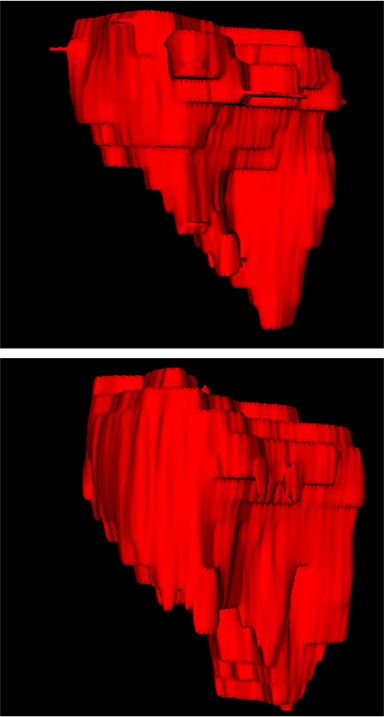

Refer to caption

(a) DSC=0.860

(b) DSC=0.853

(c) DSC=0.821

(d) DSC=0.847

Figure 8: Examples of 3D predicted results for MMFNet. The first row are ground truth, and the second row are masks predicted by MMFNet.

Figure 10: Examples of 3D predicted results for different methods. (a) Ground truth. (b) Patch-based CNN (CET1). (c) Multi-modality patch-based CNN. (d) U-net (CET1). (e) 3D U-net (CET1). (f) Input-level fusion. (g) Merging encoders’ features. (h) MMFNet + multi-MLP + stdPool + self-transfer.

Comparison with ground truth. Some predicted results of MMFNet are shown in 2D images and 3D images in Figure 7 and Figure 8. As shown in these figures, although the shape and size of NPC are varied from each other, MMFNet can still accurately determine the regions of NPC and obtain the accurate contours of tumors. Through analyzing 2D images in figure 7, MMFNet has a capacity to fuse multi-modality MRI to reduce the confusion brought by intensity’ similarity between nearby tissues and NPC. The values of meanDSC𝑚𝑒𝑎𝑛𝐷𝑆𝐶meanDSC, meanASD𝑚𝑒𝑎𝑛𝐴𝑆𝐷meanASD and meanHD𝑚𝑒𝑎𝑛𝐻𝐷meanHD of MMFNet are shown in Table 1. MMFNet can reach the best results with DSC=72.38%,meanASD=2.07mmformulae-sequence𝐷𝑆𝐶percent72.38𝑚𝑒𝑎𝑛𝐴𝑆𝐷2.07𝑚𝑚DSC=72.38\%,meanASD=2.07mm, and meanHD=18.31mm𝑚𝑒𝑎𝑛𝐻𝐷18.31𝑚𝑚meanHD=18.31mm.